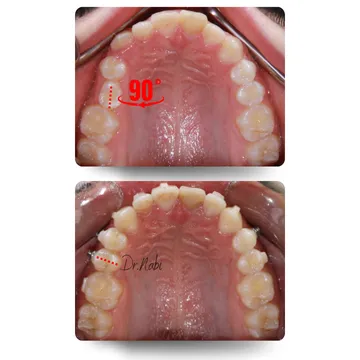

در این بخش تعدادی از کیسهای واقعی درمان شده با ارتودنسی نامرئی رو میبینی. تصاویر قبل و بعد، میزان نامرتبی دندونها، نوع اصلاح انجام شده و مدت زمان درمان به صورت خلاصه نمایش داده شده. تمامی درمانها تحت برنامه ریزی تخصصی دکتر نبی و با پیگیری مستمر انجام شده، تا علاوه بر بهبود زیبایی لبخند، پایداری نتیجه نیز حفظ بشه [2].

این آقای نوجون به دلیل سابقه ضربه و درمان ریشه دندان سانترال چپ بالا، محدودیت استفاده از براکت داشتیم. درمان کامل با الاینر شفاف انجام شده. روتیشن 90 درجه دندان پرمولر اصلاح ودندون نیش خارج از قوس به موقعیت صحیح هدایت شد و لبخند پایدار و هماهنگ حاصل شد.